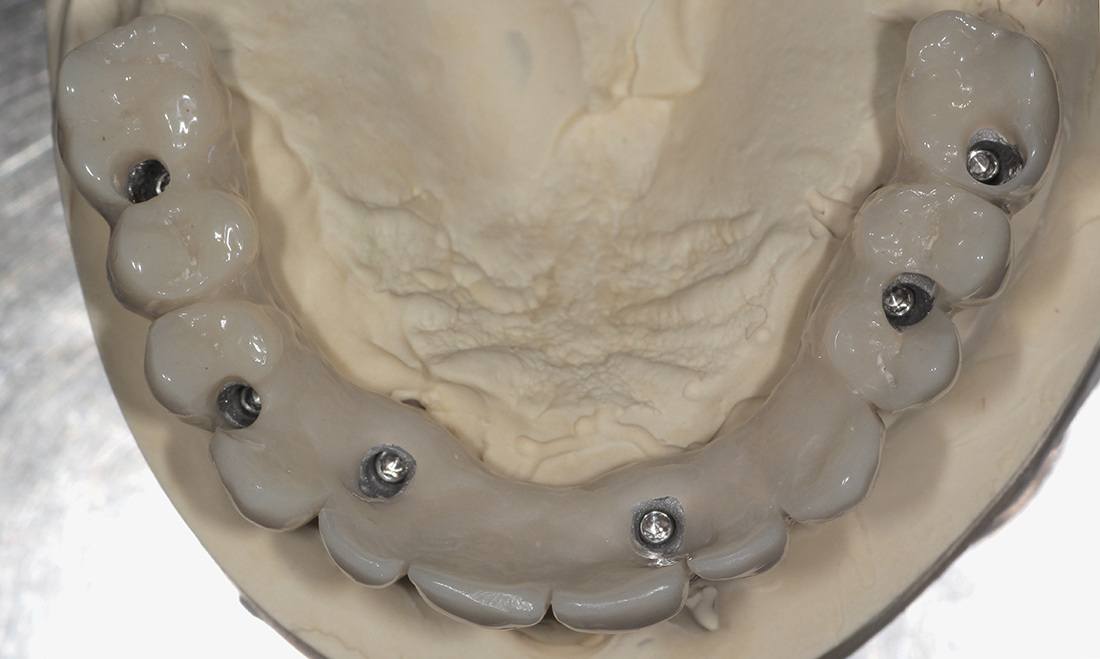

В данной ситуации мы зафиксировали шаблон, установили 6 имплантов системы «ICX Templant» (Германия), провели наращивание костной ткани, установили окончательные головки «мультиюнит» и сняли слепки для изготовления временной конструкции. Через несколько дней был готов металлопластмассовый протез с винтовой фиксацией на шести имплантах.

По прошествии трех месяцев пациентка была направлена на окончательное протезирование. Так за минимальный срок мы смогли избавиться от съёмного протеза и получить фиксированную конструкцию на имплантах, гораздо более удобную и функциональную.